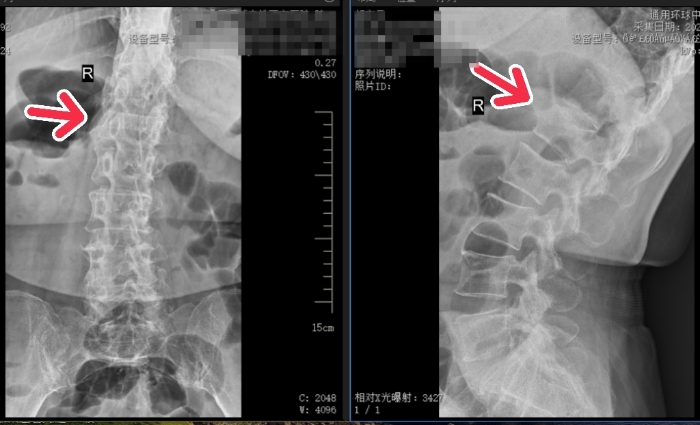

上:术前 / 下:术后

患者血压较高,姬传磊主任团队术前请心血管病院副院长何丽会诊,并制定了周密的手术方案及应急预案。手术团队凭借丰富的经验和娴熟的技术,为患者成功实施了腰1椎体压缩性骨折椎体成形术。

在医护团队的悉心照料下,患者术后次日便可佩戴腰围坐立和下床活动,腰背部疼痛显著缓解,患者及家属对手术效果表示满意,并对姬传磊主任及全体医护人员的精湛医术和贴心服务表达了诚挚谢意。